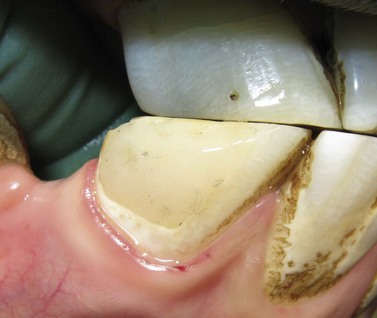

Fig. 21.13 Application of Type II glass ionomer (GI) cement restoration. GI restorations should only be applied after careful and cautious planning because of the hypsodontic eruption of equine teeth. (A) Tooth resorption on the vestibular aspect of the 3rd incisor of a senior horse. (B & C) Cavity preparation of the lesion involved osteoplasty and extensive subgingival debridement of all three dental tissues

(Modified Honma Stage 3 lesion).

image

(D & E) A glass ionomer restoration was selected due to the uncertain etiology of the lesion and based on extrapolated applications in human and small animal patients. (F) 1-year follow-up demonstrates retention of the restorative with surface pitting and possible marginal leakage.